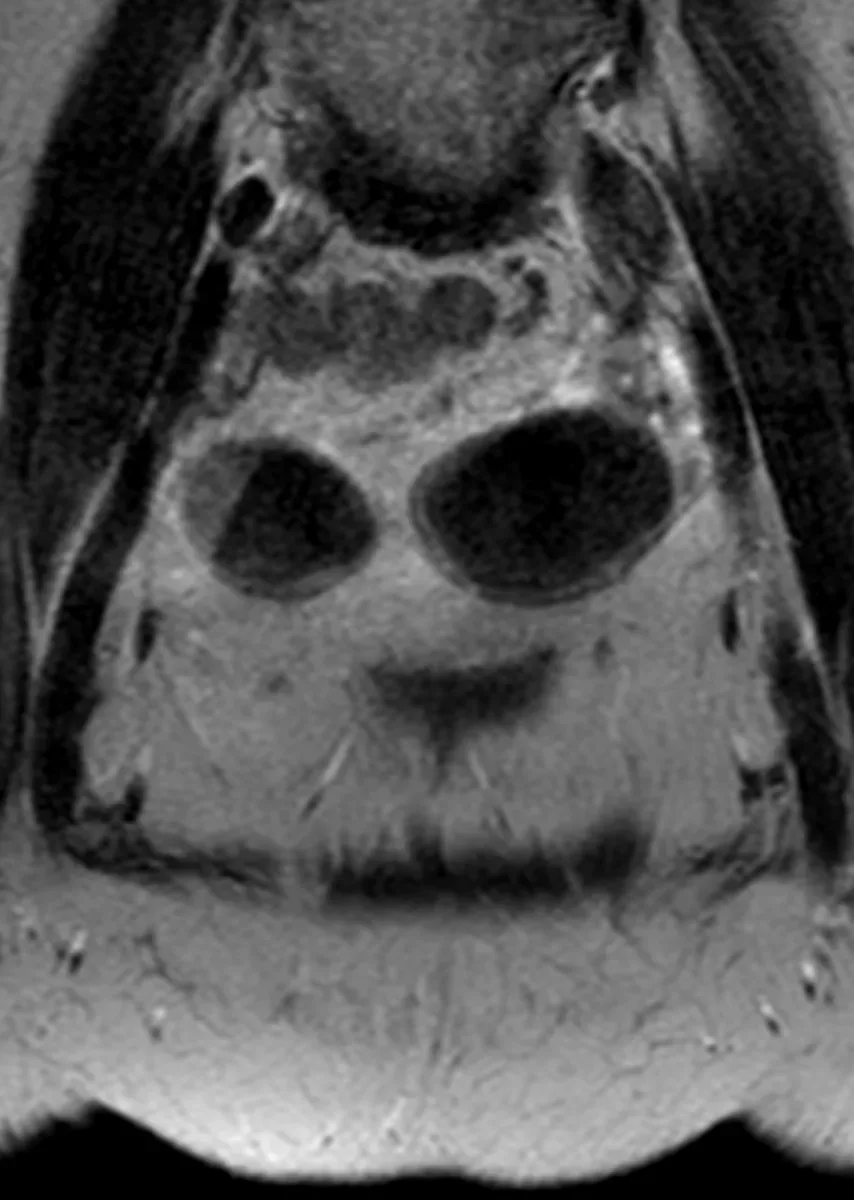

Плексиформная кожная нейрофиброма у мужчины 34 лет с известным диагнозом Нейрофиброматоз первого типа. В отличие от типичных мишеневидных поражений, идущих вдоль крупных нервов при глубоких плексиформных нейрофибромах, поверхностные плексиформные нейрофибромы при НФ1, как правило, асимметричны, имеют немишеневидную структуру, не обладают узловатой или фасцикулярной морфологией и поражают кожу, а не только клетчатку. У этого пациента, как он говорит, шишка на внутренней поверхности левого бедра в течение многих лет, не меняется.